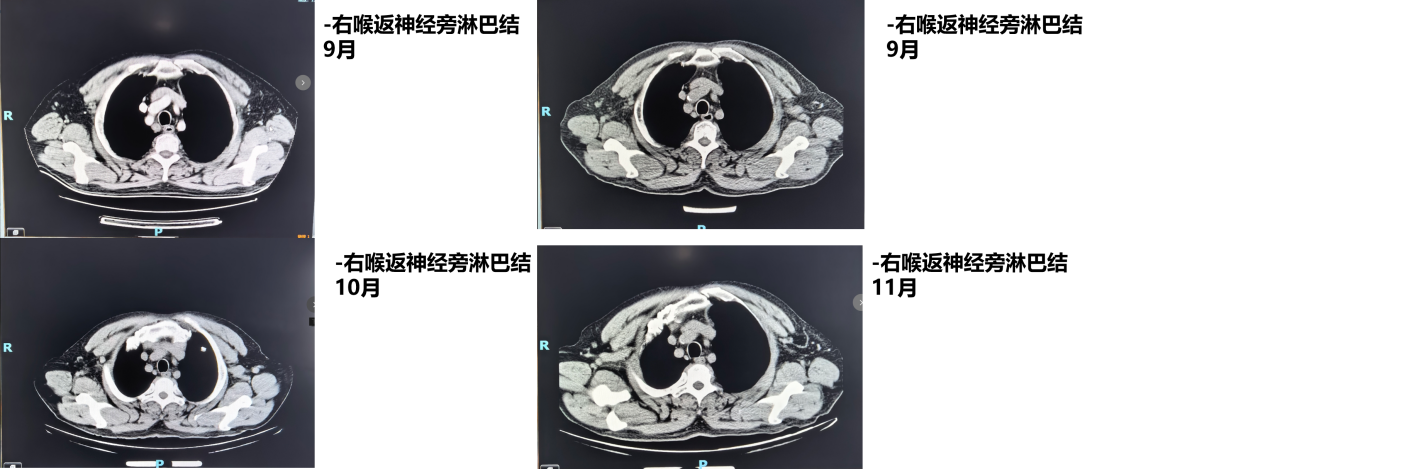

1周期后(2025年9月)复查CT:食管病变、纵隔淋巴结较前减小,双肺转移结节较前部分减小。1周期即显现疗效。

4周期后(2025年11月)复查CT:与2025-10-17日图像对比,食管癌治疗后改变,同前相仿;纵隔淋巴结治疗后改变,较前减小;双肺多发小结节,考虑转移瘤治疗后改变,部分较前略减小。

疗效评估:达到部分缓解(PR)

本例患者PD-L1 CPS评分为3分,属于CheckMate 648研究中获益更为显著的PD-L1阳性人群。经过4个周期纳武利尤单抗联合化疗后,影像学复查显示原发灶及所有转移病灶均明显缩小,疗效评估达PR,与研究中PD-L1阳性患者高达53%的ORR相符。